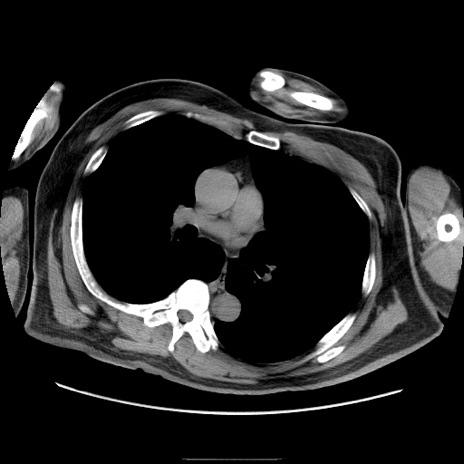

症例

冠状断像